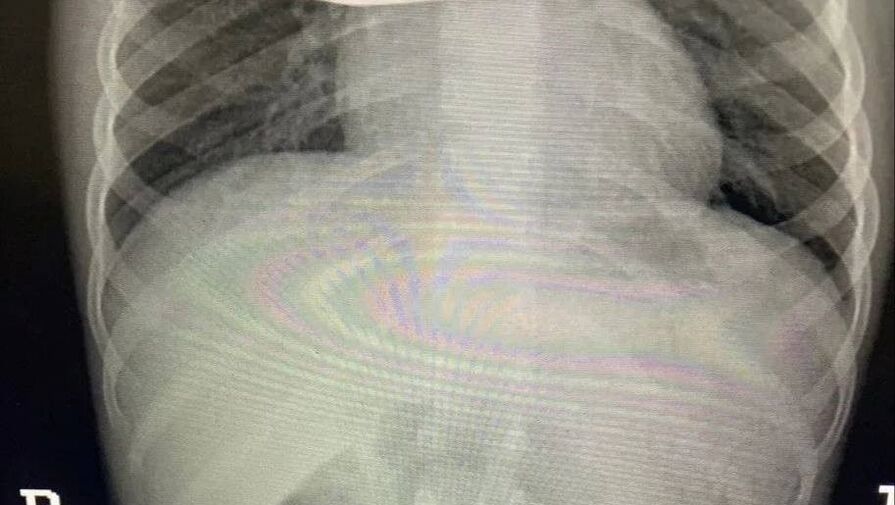

Инцидент произошел в Балашихе — малолетнюю пациентку с жалобами на острую боль в животе доставила в больницу бригада скорой помощи. Обследование показало, что внутри у ребенка большое количество металлических инородных тел. Девочку немедленно отправили на операционный стол.

Врачи приняли решение обойтись без полостного вмешательства. Через крошечные проколы специалисты аккуратно извлекли 20 магнитов из организма ребенка — они успели притянуться друг к другу и прожечь стенку кишки насквозь. Пять штук и вовсе мигрировали в область малого таза.